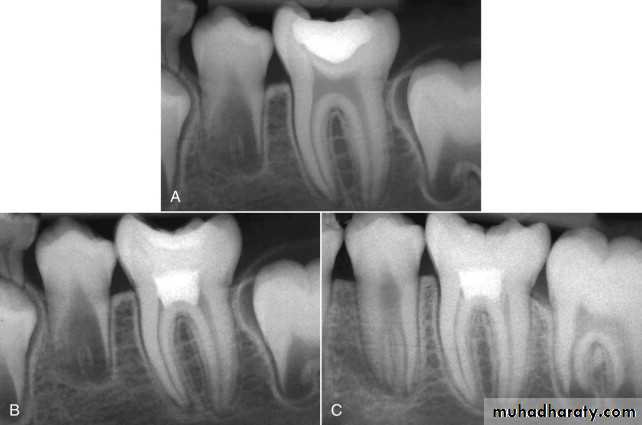

PULPAL CALCIFICATIONS

Calcification of pulp tissue is a common occurrenceIn the coronal pulp, calcification usually takes the form of discrete, concentric pulp stones.

Pulp stones (denticles) range in size from small, microscopic particles often seen in association with the wall of arterioles to accretions that occupy almost the entire pulp chamber.

Luxation of teeth as a result of trauma may result in calcific metamorphosis, a condition that can, in a matter of

months or years, lead to partial or complete radiographic obliteration of the pulp chamber. The cause of radiographic obliteration is excessive deposition of mineralized tissue resembling cementum or, occasionally, bone on the dentin walls, also referred to as internal ankylosis

Clinically, the crowns of teeth affected by calcific metamorphosis may show a yellowish hue compared with adjacent normal teeth.

Continued formation of secondary dentin throughout life gradually reduces the size of the pulp chamber and root canals.There is a gradual decrease in the cellularity and a concomitant increase in the number and thickness of collagen fibers